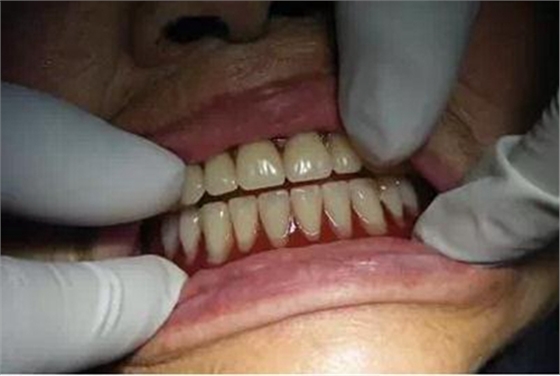

患者戴入后,感到義齒穩(wěn)定性明顯的增強(qiáng)了。

經(jīng)過(guò)簡(jiǎn)單的調(diào)合后,患者戴走適應(yīng)。

一個(gè)星期后復(fù)診,經(jīng)檢查只有左下頜頰、舌側(cè)有兩個(gè)壓痛點(diǎn),調(diào)改后不再疼痛。

另外,她感到下頜還有些松動(dòng)。經(jīng)檢查,我認(rèn)為是下頜義齒與頰側(cè)的黏膜空間有些大,唇頰側(cè)的黏膜沒(méi)有對(duì)義齒形成夾持力,經(jīng)襯墊處理后,能明顯的感到義齒的穩(wěn)定性以及吸附力增加了。

中午與患者一起吃午飯,患者對(duì)義齒的咀嚼效率也很滿(mǎn)意,戴走后兩個(gè)月至今沒(méi)有再?gòu)?fù)診。